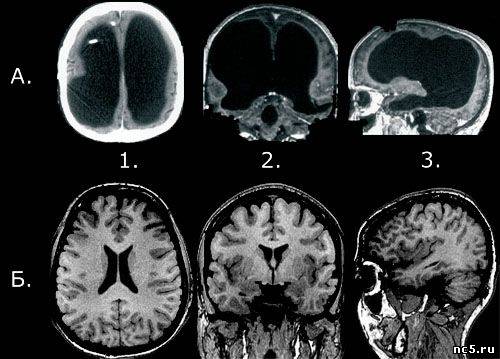

Сравнение мозга клерка из Марселя (в верху) с мозгом нормального человека (внизу):

1. Аксиальный срез (вид сверху);

2. Фронтальный срез (вид спереди);

3. Сагиттальный срез (вид сбоку).

Снимок 1А сделан при помощи компьютерной томографии (КТ), остальные — при помощи магнитно-резонансной томографии (МРТ).